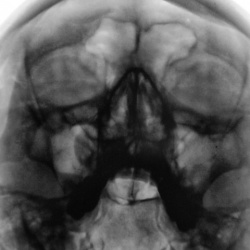

Рутина... Пациент направлен на рентгенографию ППН.

Пациент направлен на рентгенографию ППН отоларингологом.

Пациент направлен на рентгенографию ППН.

Пациент направлен на рентгенографию ППН отоларингологом